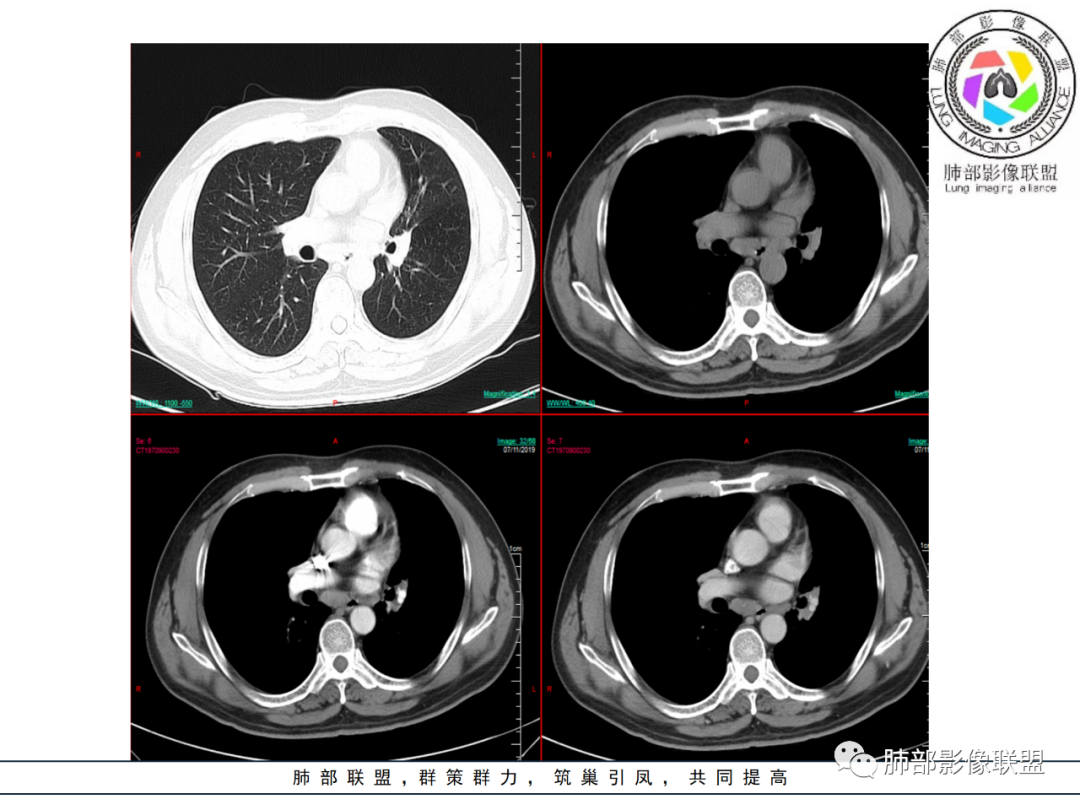

临床及影像所见:

1.中年男性,咳嗽咳痰一月余,无咯血。 医学百科网 | YxBaike.Com

2.左肺上叶肺门区见不规则块影,前方边界不可分。主动脉窗结节影边界稍模糊且与肺门块影融为一体。密度均匀,未见钙化及液化。相邻肺血管影轻度受压。 医学百科网 | YxBaike.Com

3.左肺上叶前段支气管及其分支狭窄闭塞。 医学百科网 | YxBaike.Com

左肺上叶舌段重度狭窄并见腔内软组织影突入。

注意,支气管的狭窄或闭塞是多处多段的!

4.左肺上叶体积缩小,其中前段不张并萎陷纵隔旁。 医学百科网 | YxBaike.Com

5.肺门块影及不张肺组织均轻到中度强化,未衬托出低密度块影。

6.隆突下见增大淋巴结,环形强化为主。 医学百科网 | YxBaike.Com

7.纵隔左移(而非纵隔冻结)。提示病程漫长或存在相关基础疾病。

8.左肩胛骨旁动脉期血管影显示,疑逆流或回流受阻。扫描范围内肩胛骨及肋骨等未见明显骨质吸收破坏。 医学百科网 | YxBaike.Com

1.肺鳞癌:较大支气管阻塞伴肺不张,病灶强化不显著等,总会首先想到肺鳞癌。

但多处支气管狭窄或闭塞(前段和舌段两处相距还有点远),用肺鳞癌解释有点牵强。

增强扫描肺门区并未能勾画出一个低密度的块影。

此外,52岁的年龄对于肺鳞癌还是稍显年轻。 医学百科网 | YxBaike.Com

2. 小细胞癌:异常肿大淋巴结可以形成肺门区多处支气管管腔狭窄。

但小细胞癌增大的纵隔淋巴结往往十分凸显,肺野常常较干净。

支气管隆突下增大淋巴结通常不符合左肺上叶癌肿的迁徙途经。 医学百科网 | YxBaike.Com

纵隔的移位也非一朝一夕。

3.慢性感染:累及较大支气管且形成块影,常见的有支气管侵袭性曲霉病等真菌感染及结核等。

患者非易感人群,病灶较为局限,曲霉病等真菌感染缺乏支持点。 医学百科网 | YxBaike.Com

结核病常见,正如有老师分析,应当纳入考虑范围。支气管多处狭窄,或断断续续,符合结核的特点。 医学百科网 | YxBaike.Com